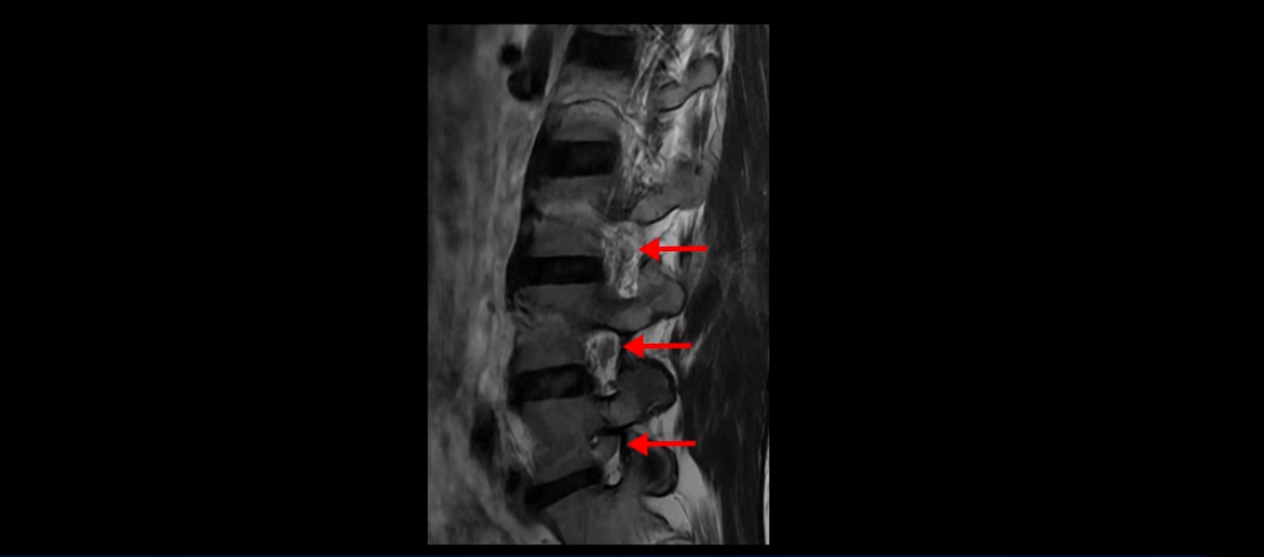

우선 이분 허리 MRI를 보면 5번 1번에 퇴행성 디스크가 있지만 방사통을 일으킬 만큼 신경을 누르고 있어 보이지 않습니다.

오른쪽으로 디스크가 약간 찢어져 보이는데, 작년에 찍은 MRI에서도 보이는 것이라 오래 전에 찢어진 후 아문 흔적으로 보입니다.

중요한 것은 오른쪽 다리에 심한 방사통이 있다든가 재채기를 못 한다거나 허리를 구부리거나 몸을 살짝 비틀 때 날카로운 통증이 없습니다. 즉, 섬유륜이 최근에 찢어진 게 아닌 겁니다.

4번 5번과 3번 4번 마디도 디스크가 중앙으로 살짝 밀려나와있지만 최근에 섬유륜이 찢어진 것도 아니고, 신경 다발을 누를 정도로 심하게 밀려나와 있는 것도 전혀 아닙니다.

양쪽 신경 가지가 빠져나가는 추간공도 충분히 넓어서 신경학적 방사통을 일으킬 여지가 없습니다.